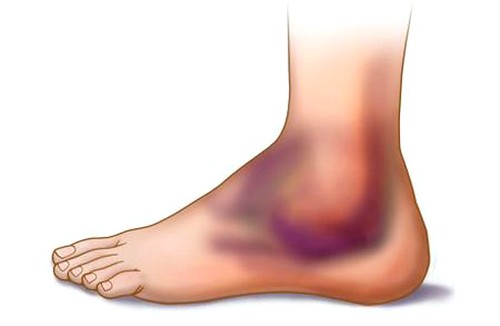

Признаки интоксикации отсутствуют. Сразу после травмы возникает отек, который в первые часы не имеет четких границ. Он локализуется в области связок, но со временем может увеличиваться и распространяться на лодыжку. Степень выраженности отека зависит от тяжести травмы и может сохраняться в течение 2–3 недель.

Полный разрыв всегда сопровождается образованием кровоподтеков из-за повреждения сосудов. Возможно развитие гемартроза, при котором в суставной полости скапливается кровь. Кровоподтеки могут быть значительными, и опытные врачи часто сталкиваются с такими травмами. Для них характерно резкое ограничение подвижности.

Голеностопный сустав становится нестабильным, так как связки не могут выполнять свои функции. Контуры сустава сглаживаются, нарушается конгруэнтность (правильное сопоставление костей в суставе). Пострадавшему трудно опираться на ногу, и разрыв связок чаще всего наблюдается с одной стороны. При нажатии на голень возникает резкая боль, что приводит к хромоте. В запущенных случаях могут возникнуть осложнения, включая инфекцию.